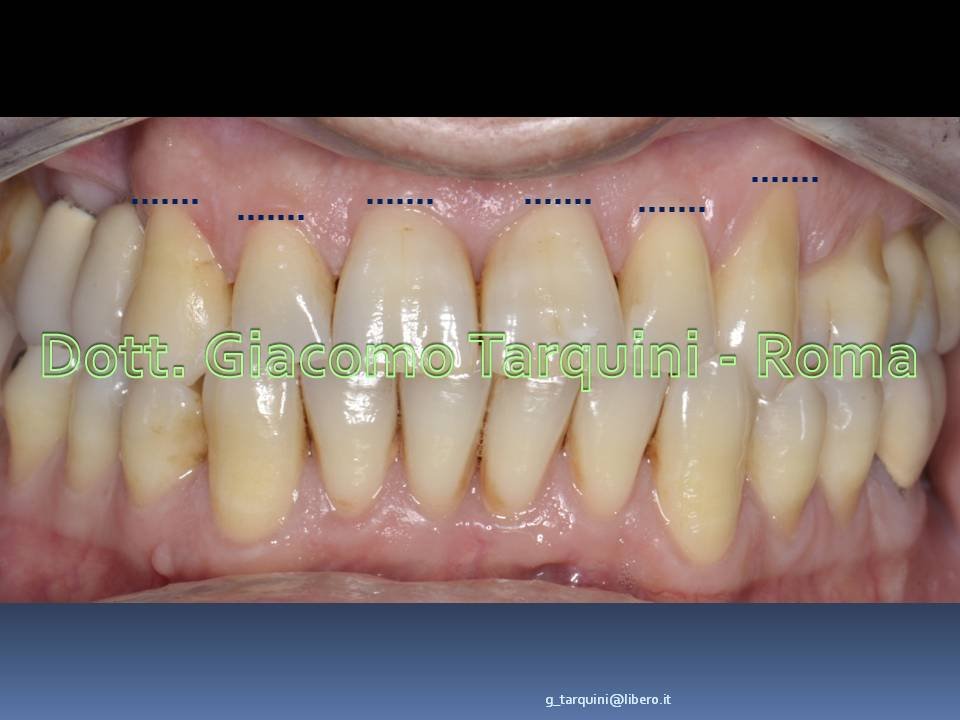

Foto cliniche preoperatorie

Viene posta diagnosi di recessione di Classe 1 sec. Miller associata ad erosione cervicale.